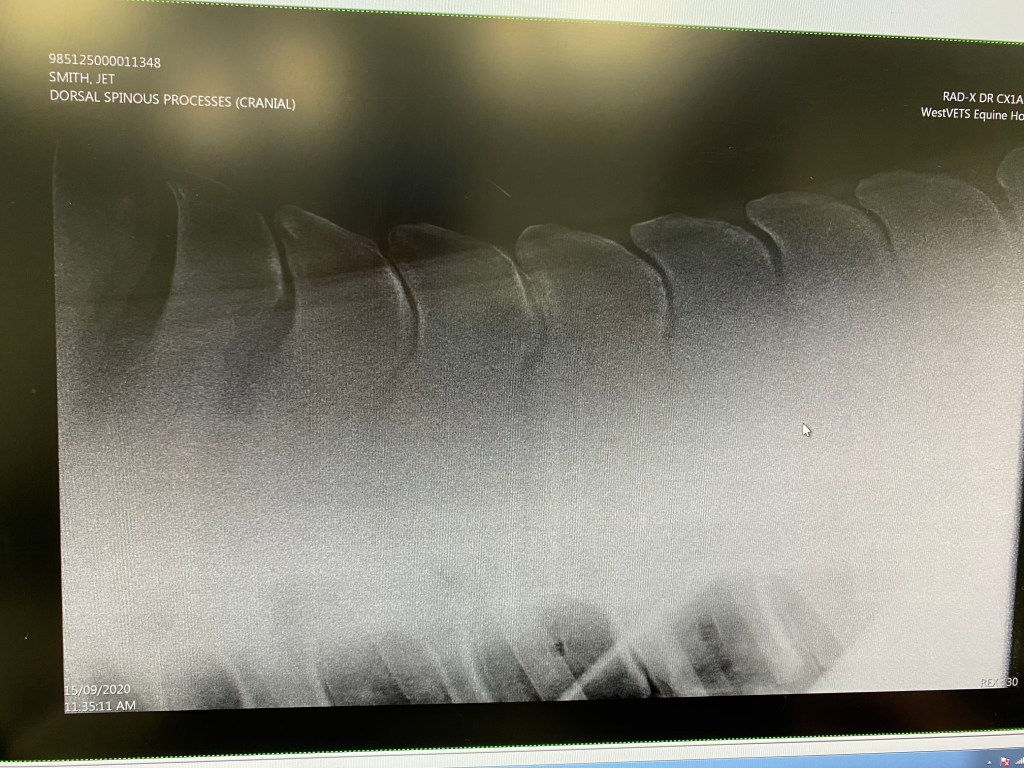

Theo- a horse I took on from a client due to him being overly anxious and throwing in the occasional buck was concerning me. Despite him being a lovely mover and scopey jumper he was so difficult to get him to relax his back, it felt as though he was a bomb about to go off, he would literally hold his breath until you walked. He would also disunite and bunny hop in the canter. I thought it was time to investigate the reason-> X-rays of his back revealed some kissing spines. We injected his back with some steroids as well as his hocks and waited to see whether there was much improvement.

Jet was no longer happy jumping, he was getting very upset on the landing side of the fence and going rather silly, rushing and bucking which then resulted in him injuring himself. This then progressed to resisting to canter altogether. I was devastated, stressed and wanted to get him sorted asap. Foxy was suddenly having to step in as numero uno while I figured out what to do with Jet. After multiple trot ups, flexion tests, nerve blocks and injections of hocks and sacroiliac we ended up having to x-ray his back and found he also had some impinging dorsal spinous processes (kissing spines) 😦

We blocked Jet’s back to see if we could get rid of his lameness and get him cantering, but on the first attempt we didn’t. We went through it a second time a week later after not enough response to having his sacroiliac joint and both hocks injected and success! Suddenly the resistance to canter disappeared and he didn’t buck. To really really check, I even jumped a few jumps, including ^1m as that is when he would usually be upset. I didn’t die therefore we decided to book him in for surgery.

This- of course was all vlogged and can be found over on my YouTube channel- don’t worry it isn’t too gorey for the faint hearted out of you all. It is super interesting for those of you that are the same horrid predicament or just a bit of a nosey parker (ha ha don’t worry- me too)